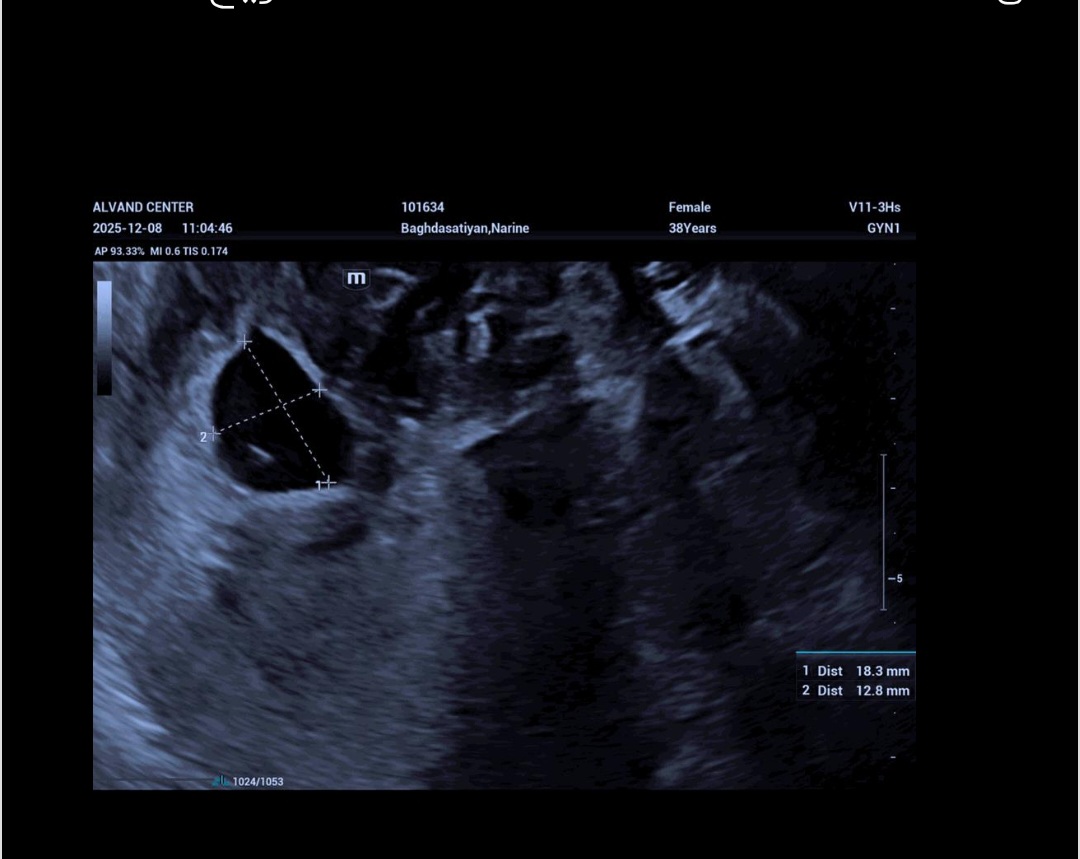

سلام دوستان خیلی نگرانم میشه کمکم کنید ۲۳ مار اخرین پریودم بود و چون فیبروم های زیادی دارم تا فهمیدم باردارم رفتم دکتر ۲۷ ابان دکتر سونو کرد و گفت تقریبا ۴ هفته ای و ی ساک کوچولو داری و برای ۳ هفته دیگه یعنی ۲۷ اذر سونو قلب نوشت و من رفتم جای دیگ سونو انجام دادم که تو سونو به علت فشار فییروم ساک حاملگی کمی دفورمه بود و گفت براساس سایز ساک ۱۰ میلیمتر بود ۶هفتمه و کیسه زرده و قلب دیده نشد و گفت به احتمال خیلی زیاد بارداری پوچه و امید نداشته باش و امروز رفتم پیش دکتر خودم قرار شد هفته دگه دوبار سونو بدم بنظرتون بارداری پوچ امید نداشنه باشم؟

میدونم چون ۲۷ ابان دکتر گفت ۴ هفتنه رو اون حساب ۱۷ اذر باید ۷ هفته و ۵روزم میشد ولی سونو ۶ هفته نشون داد

مرسی عزیزم خیلی بهم استرس دادن دکتر گفت هفته دیگه دوباره سونو بده ولی صبر میکنم ۲ دی میرم که ۸ هفته کامل یشه